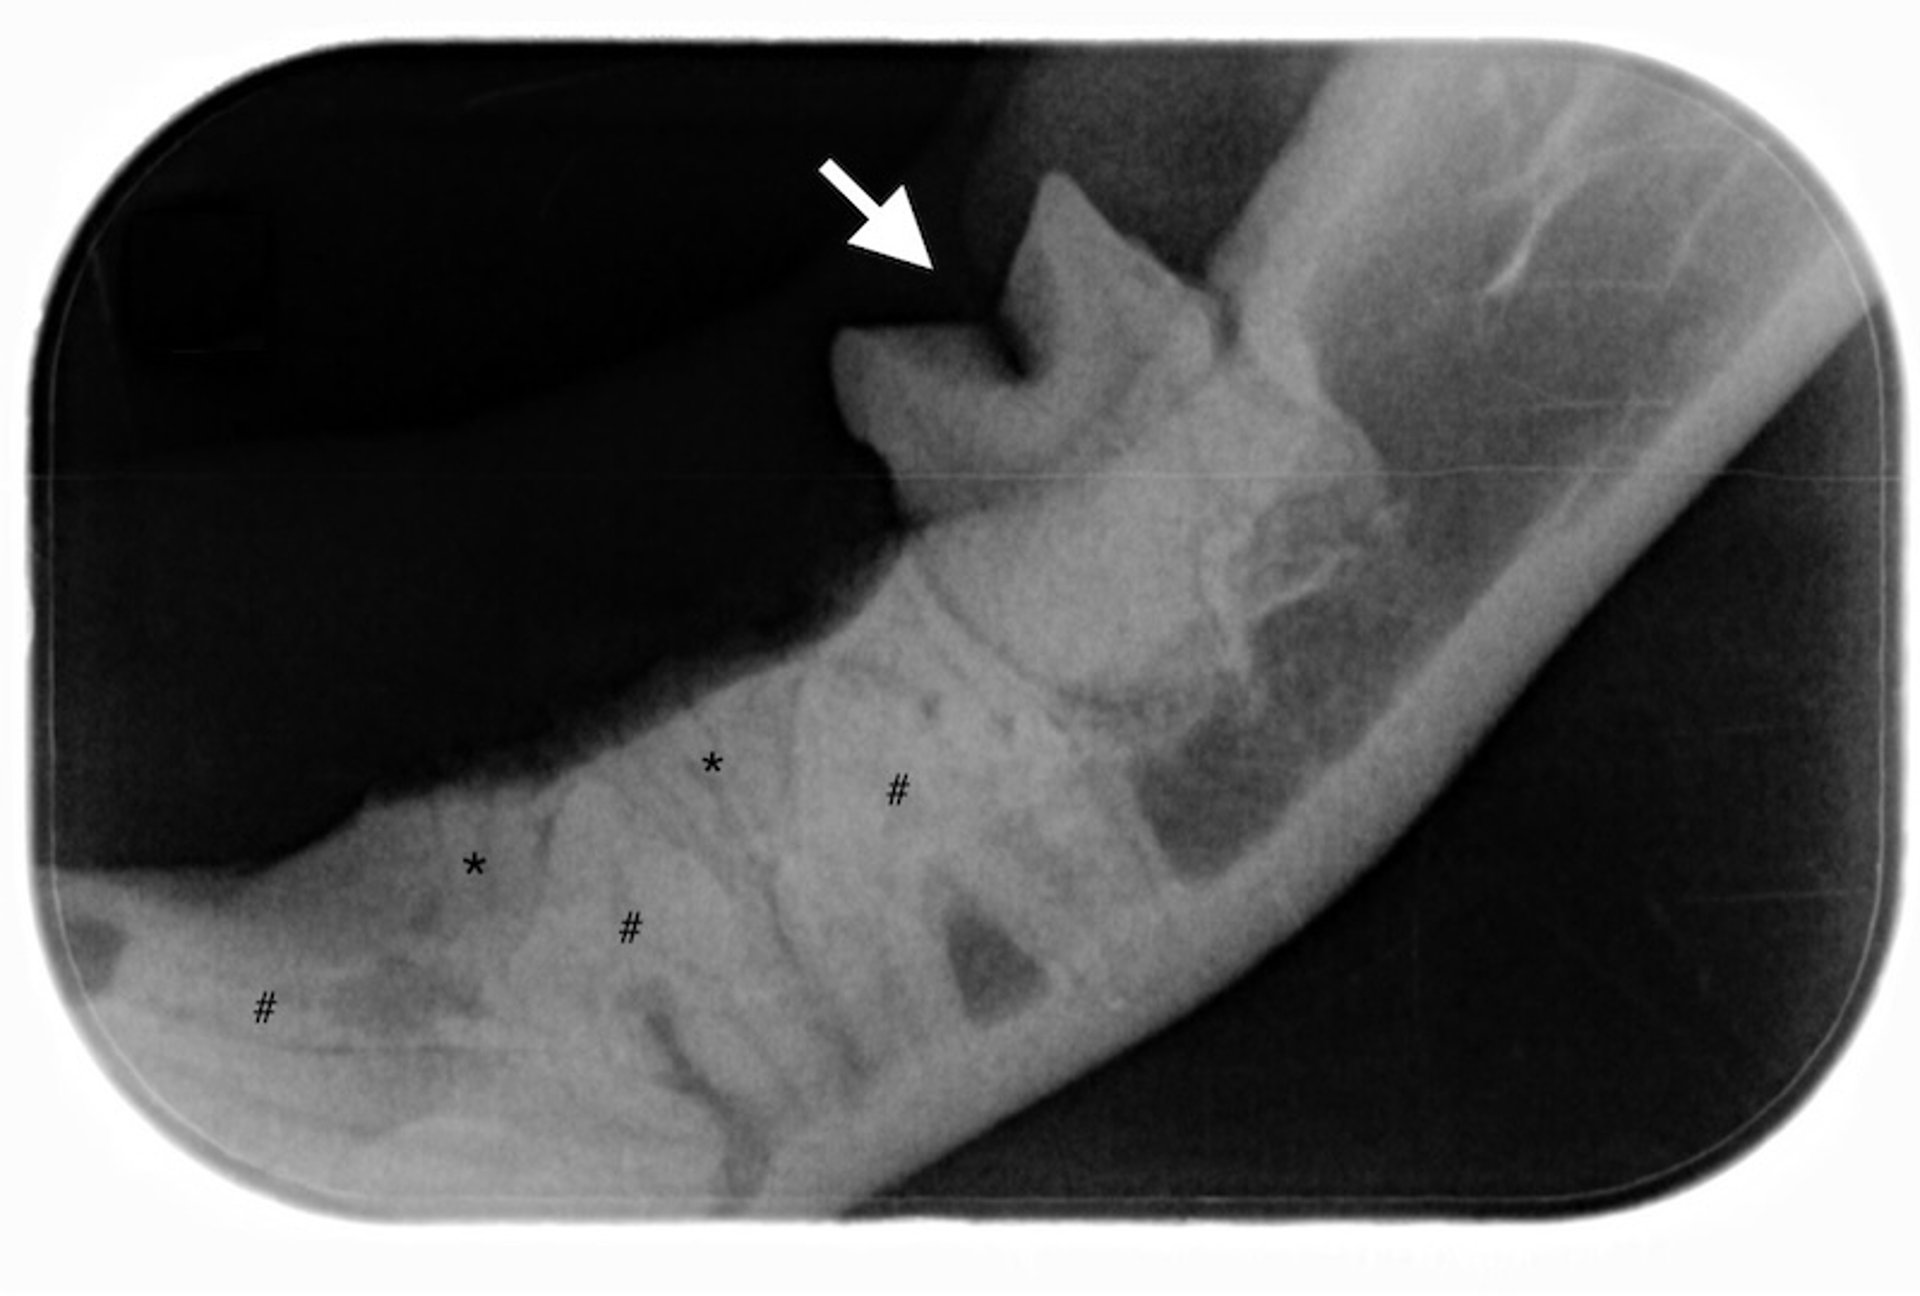

Radiography reveals bilateral bone proliferation in the mandibles and tympanic bullae. On radiographs, craniomandibular osteopathy appears as irregular bone proliferation, often affecting the mandible, tympanic bulla, and temporomandibular joint. Concurrent otitis externa and craniomandibular osteopathy may exacerbate discomfort and should be managed concurrently. In severe disease, craniomandibular osteopathy leads to numerous complications:

• intense pain on jaw movement

• inability to fully open the mouth

• mechanical or bony fusion of the temporomandibular joint

• marked difficulty in grasping and chewing food

• severe drooling

• facial swelling

• substantial weight loss due to malnutrition

• chronic otitis

• nasopharyngeal narrowing

• external ear canal stenosis

Neurological deficits can result if the bone proliferation compresses brain structures.